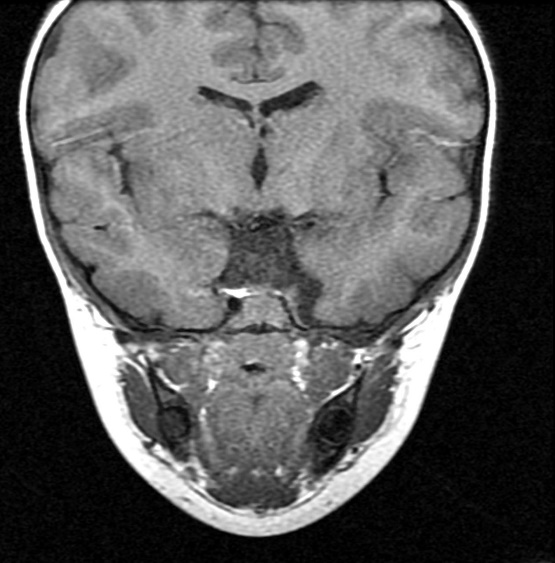

MRI findings showed the lack of the normal flow void of the left internal carotid canal and the first part of the left middle cerebral artery (Figures 1 and 2). The pituitary gland is flat. No evident anterior or posterior pituitary gland tissue or pituitary stalk is observed. The pituitary gland's strong posterior signal is not detected in situ or

ectopic. The left medial cerebral artery originates within the posterior circulation, and the left internal carotid artery cannot be seen. No intra, supra, retro or parasellar masses. Normal MRI appearance of the optic chiasm and corpus callosum. Otherwise, normal MR appearance of the brain parenchyma with no definite focal lesions. Diagnosis of congenital panhypopituitarism associated with agenesis of ICA was made.

a)

b)

c)

d)

Figure 1. a-c) figures showing MRI brain sagittal views of the patient where the pituitary sella is flat. No obvious anterior or posterior pituitary gland tissue or pituitary stalk is seen. The posterior pituitary bright signal is not visualized in site or ectopic. d) coronal MRI scan showing absence of pituitary gland tissue.

Generally, no intra, supra, retro, or parasellar masses. Normal MRI appearance of the optic chiasm and corpus callosum. Otherwise, normal MR appearance of the brain parenchyma with no definite focal lesions.